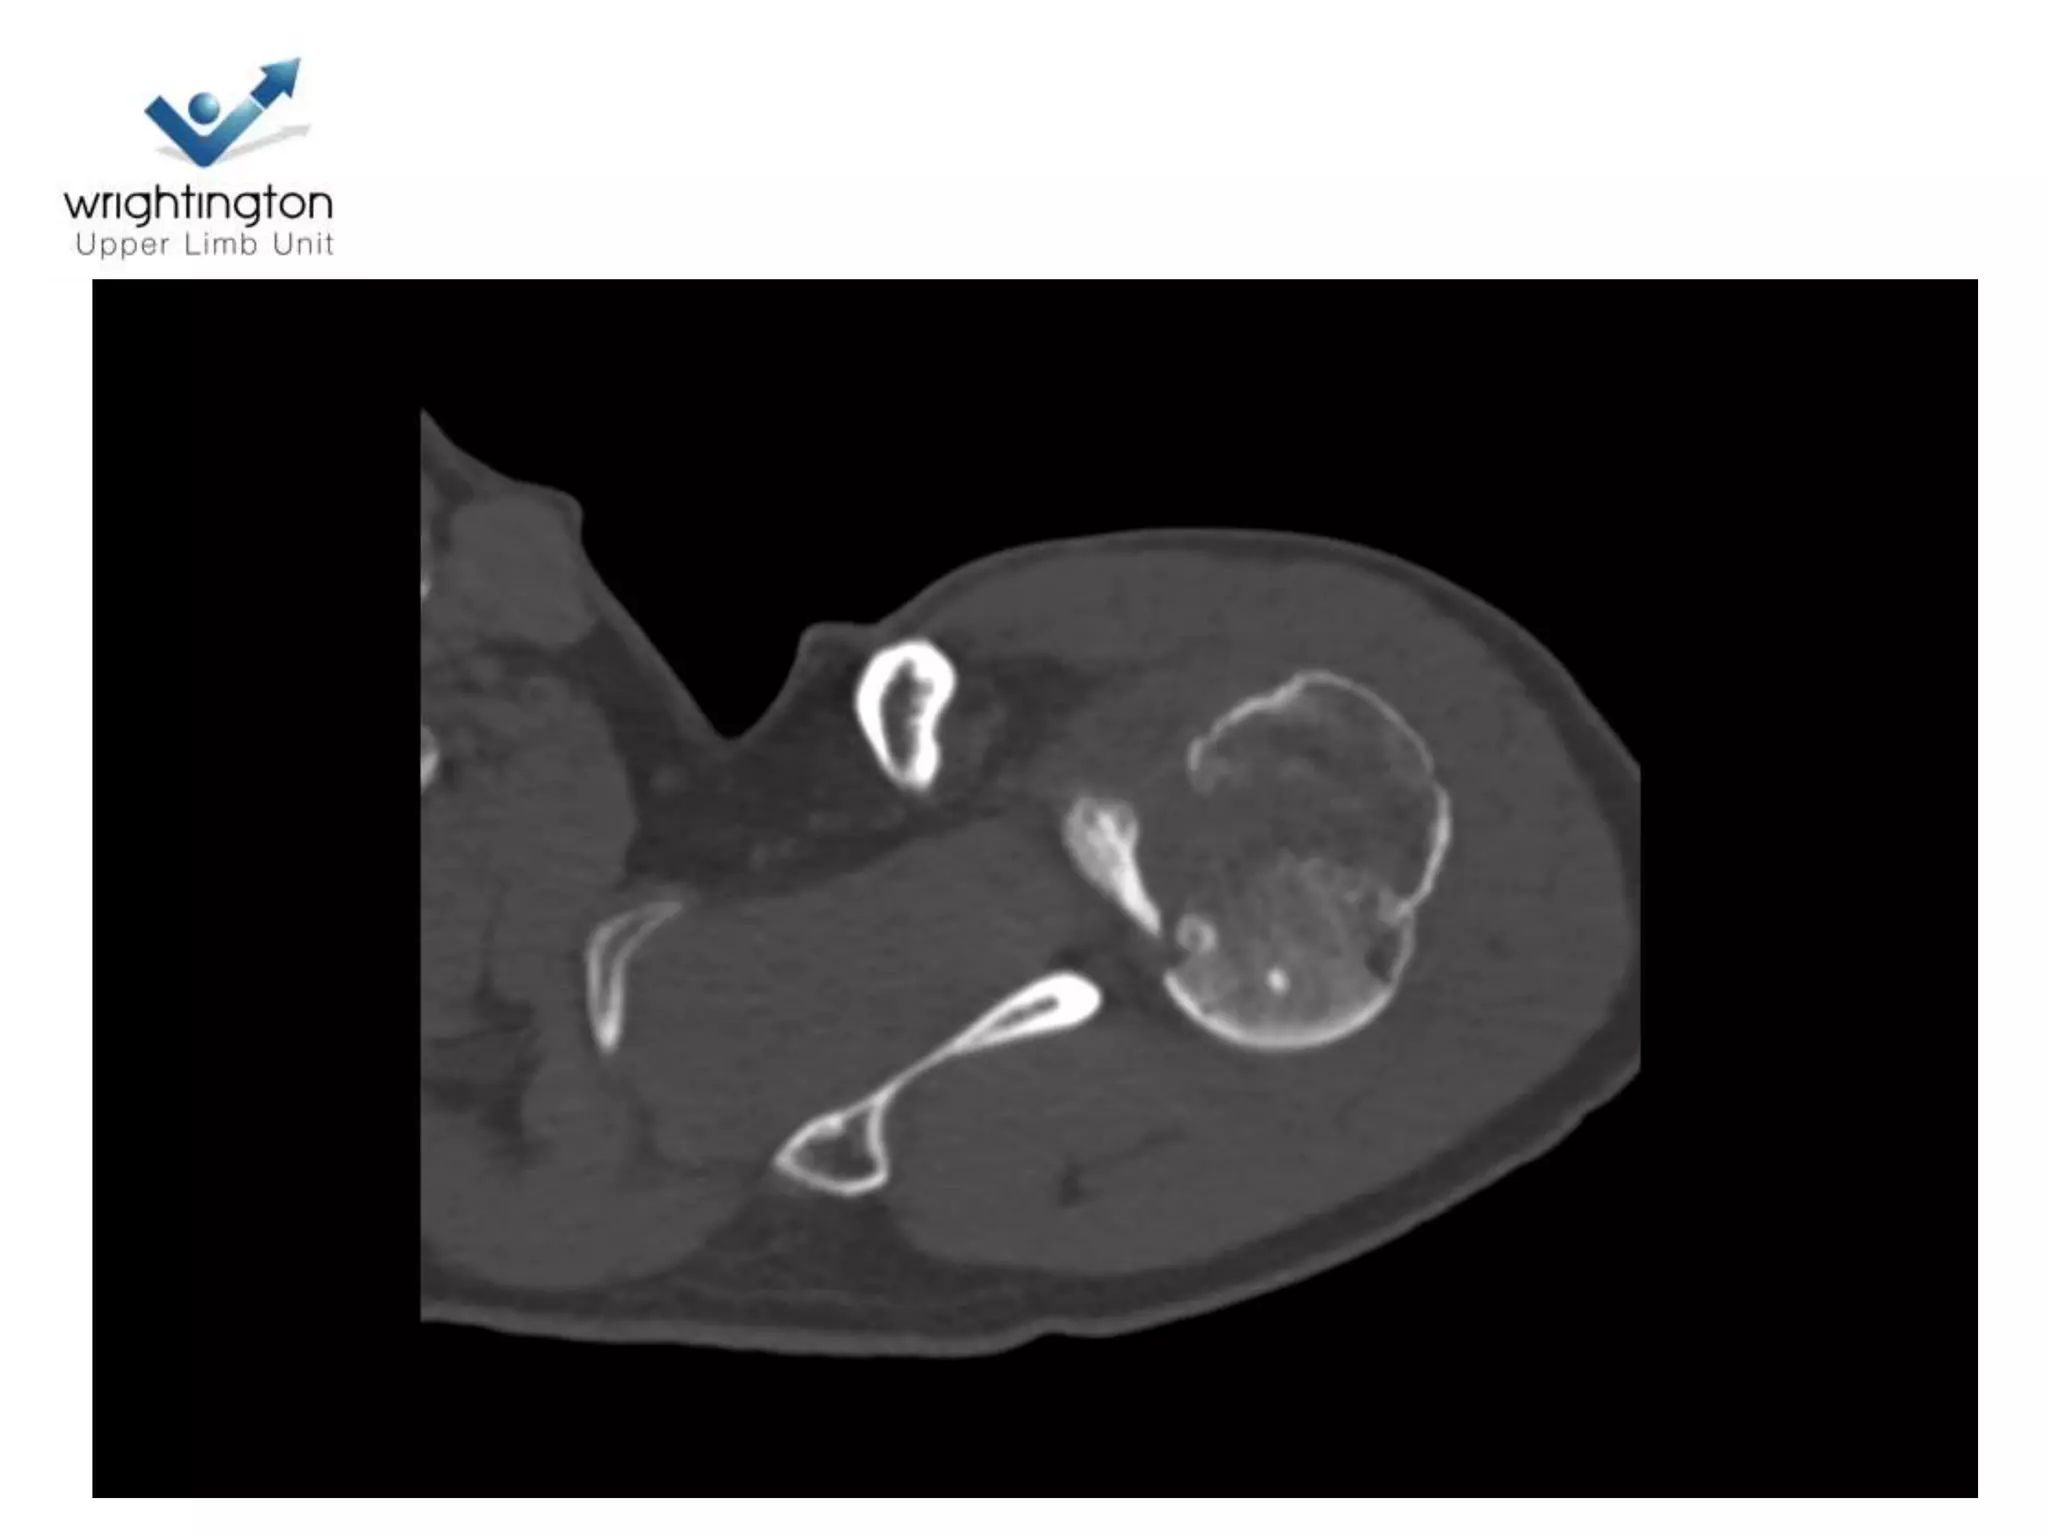

Head Ischaemia

1. Posteromedial Calcar

Predictor no 2.Medial Hinge

Medial Hinge